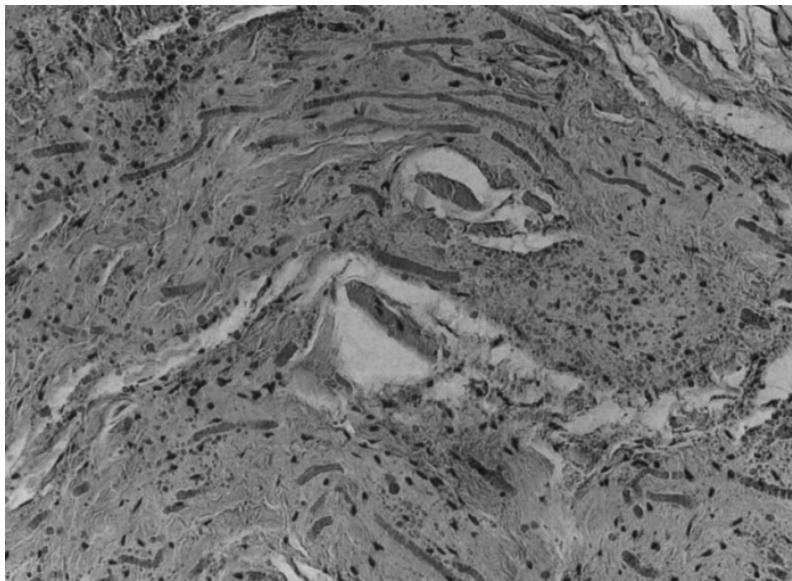

Thus, already by 1969, elastofibroma was described in some detail on the basis of not only a histological study, but also a biochemical one. Chemical analysis showed that about $8\%$ of the total dry mass of the tumor is elastin, and $75 - 80\%$ is collagen, while normal subcutaneous connective tissue contains only $2\%$ of elastin \[1\](Fig. 4).

Figure 4: Microslide. Bands of connective tissue with swollen and partially segmented elastic fibers. Both elastic fibers and collagen stain red and differ mainly in refraction. The bands are separated by loose connective tissue and fat.

The histological diagnosis is established by the presence of elastic fibers, often fragmented into a collagen matrix. In electronic microscopy: eosinophilic material often contains mature elastic fibers \[23, 28\](Fig. 5).